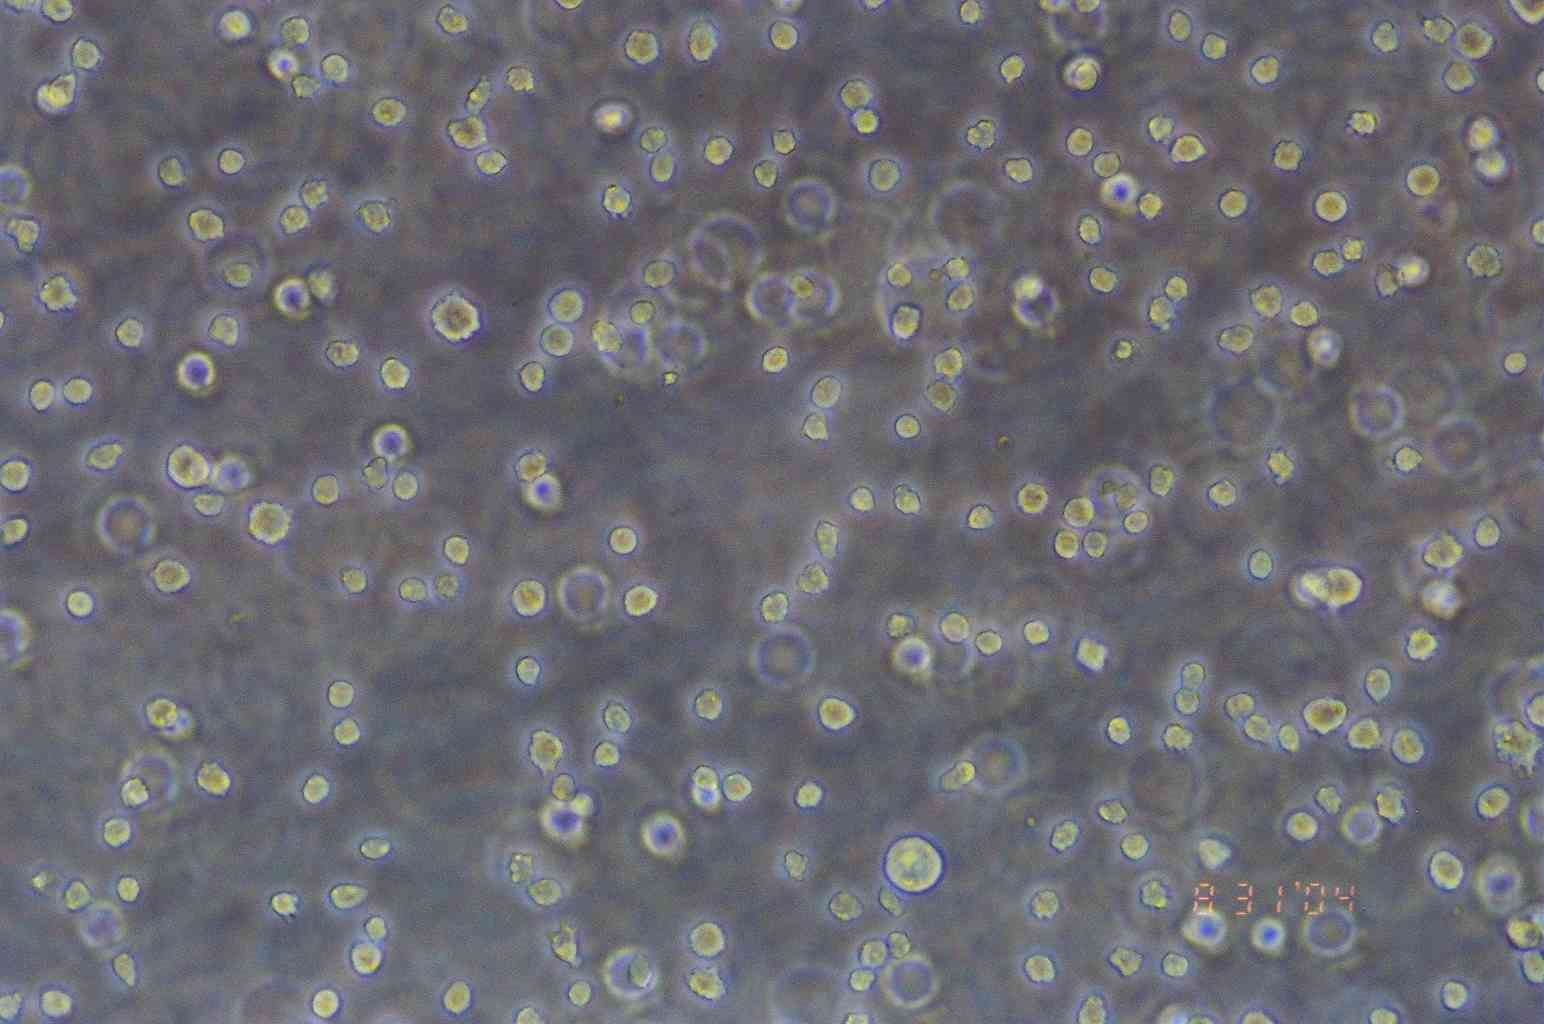

形态特征 淋巴细胞样

生长特征 悬浮